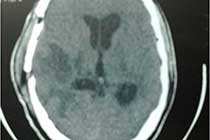

Brain Abscess Brain Abscess Post OP 2 Clinical Intra OP ,After Excising The Granuloma Intaop Scalp Abscess CT Scalp Abscess Cerebellar Abscess Post OP Clinical Cerebellar Abscess Brain TB Granuloma Post OP CT Scan Brain Infection Brain Abscess Preop MRI 2 Brain Abscess PRE OP Clinical 1 Brain Abscess PRE OP Brain Abscess Intraop 2 Brain Abscess Following Shunt Temporal Abscess T2W of TB Granuloma Scalp Abscess Preop CT Marking PRW OP MRI of TB Granuloma Post OP Clinical Photo Post OP Cerebellar Abscess Post OP Brain Abscess Intraop Specimen of Granuloma